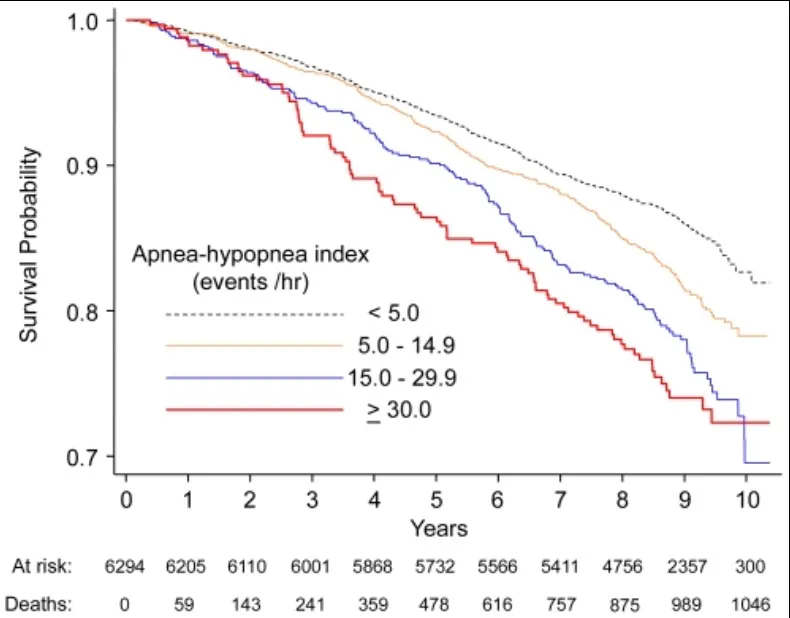

Schlafapnoe-Syndrom – Altern und Lebenserwartung

Die negativen Auswirkungen von SAS auf das Altern werden von Betroffenen und Medizinern noch nicht richtig wahrgenommen, da die meisten nur wenig über diese komplexe Krankheit wissen und die Zahl der nicht diagnostizierten Fälle immer noch recht hoch ist. (1) (s.a. Schlafapnoe-Syndrom – Diagnose)

Forscher vermuten, dass das SAS das Altern beschleunigt und verstärkt. Einerseits begründen sie dies mit den ernsten Folgeerkrankungen und andererseits mit der nachgewiesenen Erschöpfung der Stammzellen, Abnutzung der Telomere und epigenetischen Veränderungen. (2)(3)

Kaplan-Meier-Überlebenskurven in Abhängigkeit verschiedener Kategorien des Apnoe-Hypopnoe-Index und der Dauer des Schlafapnoe-Syndroms

Copyright: Punjabi et al. PLoS Med. 2009 Aug; 6(8): e1000132.